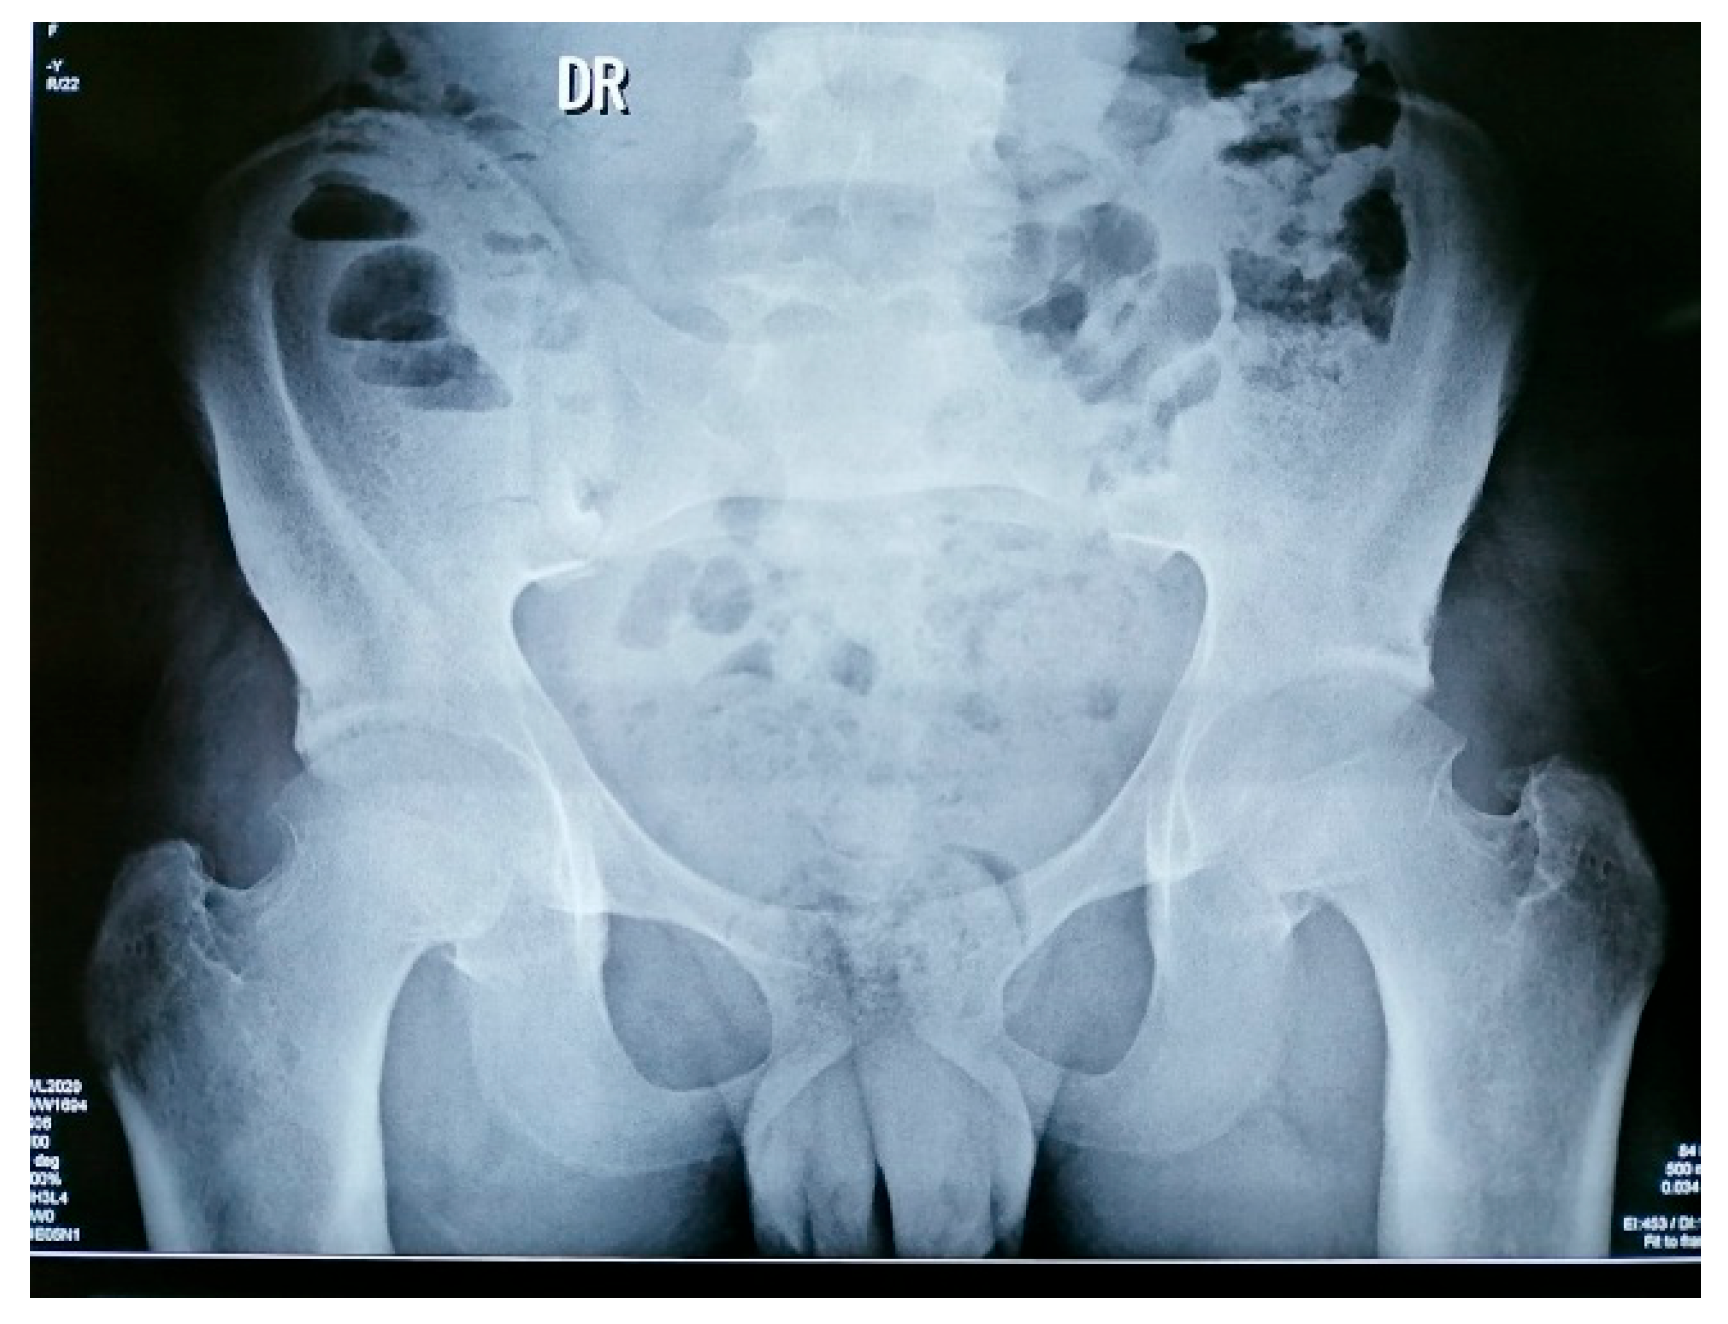

- Pelvis X-rays: acetabular osteosclerosis, bilateral reduction in coxofemoral joint space and thickened proximal femurs (Figure 5)